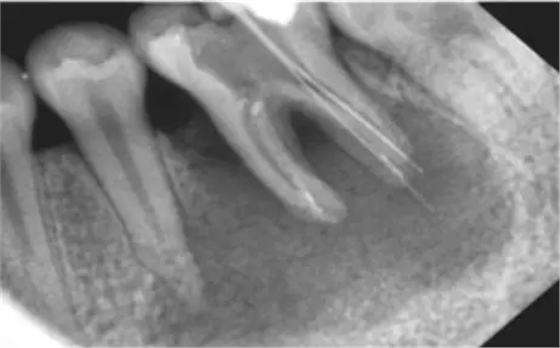

看下圖X光片是不是覺得欠充了呢?

其實(shí):X光片確定長度經(jīng)常性引起超充?

X線片法缺陷 1)三維結(jié)構(gòu)投射在二維平面上,因投射角度不一樣,數(shù)據(jù)容易出錯。 2)根尖孔不能體現(xiàn)在牙片上,而80%以上的根尖孔都不在牙齒根尖而是在側(cè)邊。 根尖開口在側(cè)邊時,X線片投射引起長度偏差錯誤。 根尖開口距離牙齒根尖距離越大,誤差越大,會引起嚴(yán)重超充。 既然手感法和X光照片法都有明顯的缺陷,那么我們應(yīng)該如何去確定準(zhǔn)確的工作長度?其實(shí)我們只要去接受現(xiàn)代根管治療的理念,使用根管長度測定儀去測定就可以。根管長度測定儀采用是電測法,是目前臨床最常見的方法,是根管治療的必備一起。測量時一個電極(唇鉤)掛于口角處,另一電極與根管銼(一般用15號k銼)相連,銼桿上的橡皮片與參照點(diǎn)接觸,當(dāng)銼尖達(dá)到根管最狹窄處時,即可測出根管工作長度。在剛開始使用根測儀時,每位醫(yī)生都會有的點(diǎn)不習(xí)慣,覺得麻煩,但是習(xí)慣后就離不開根測儀了。 獲得準(zhǔn)確的工作長度,你需要做的僅僅是改變,去使用根測儀去測量根管長度。 來源于宇森醫(yī)療